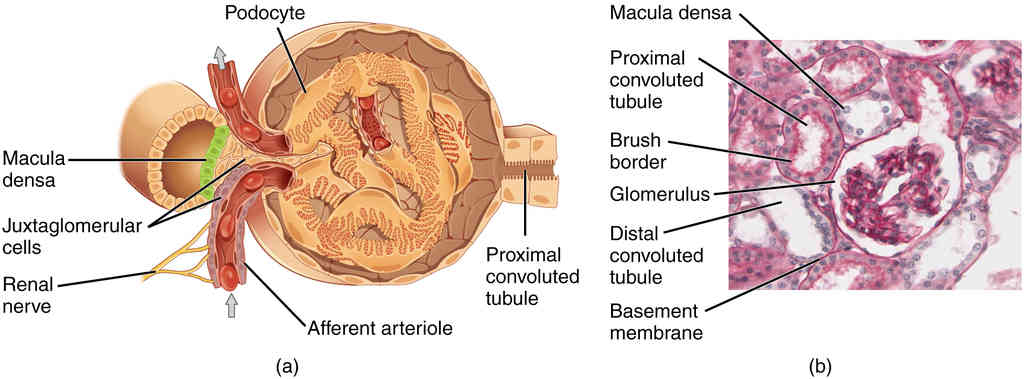

This page is under construction. For now, it is just a resource of the images found in the OpenStax Anatomy and Physiology Handbook. It wil slowly change into a revision tool. Each slide has a number. Use this to refer to the slide. When completed, it will have an unlabelled section, with labelled slides in parallel. On the unlabelled slides, write your answer and use the labelled slide to assess yourself. Keep track by also noting the number on each slide. Improvement at each attempt is important, more so than full marks on a first attempt.